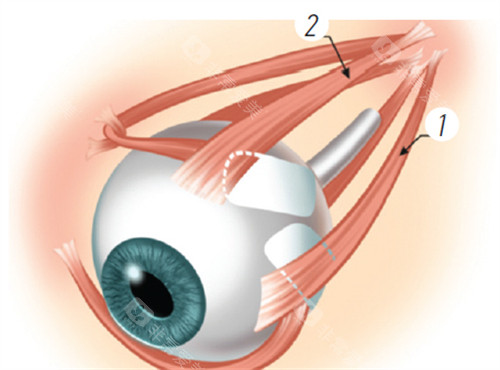

作为华北地区眼科领军品牌,朝聚眼科在角膜交联领域实现三大突破:

低温核黄素渗透技术,减少术后水肿

非接触式眼压监测系统,提升手术可靠性

智能紫外线剂量调节装置,适应不同角膜厚度

医联体模式优势

与北京同仁医院建立技术协作网络,共享角膜地形图数据库。